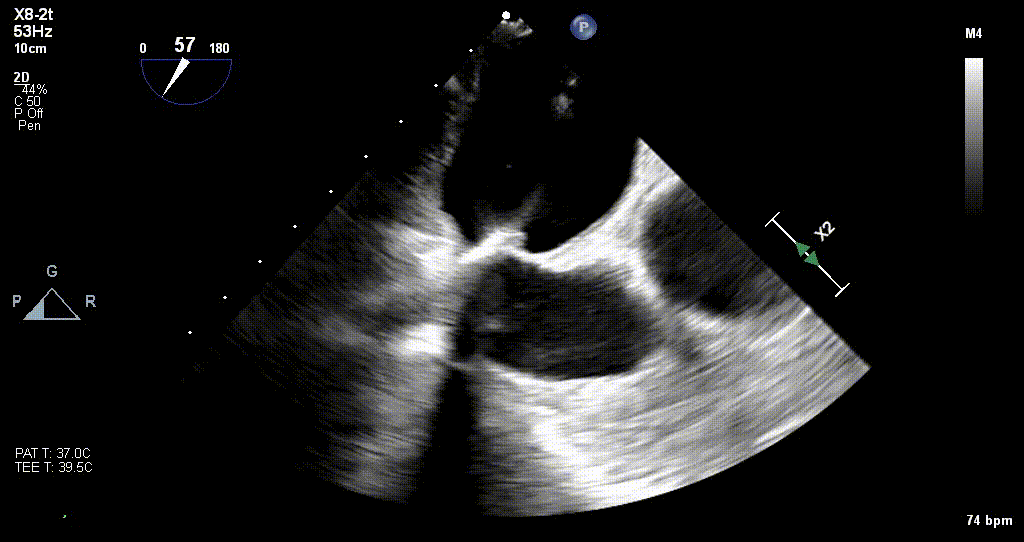

术前TEE评估

原发性MR,交界C1区脱垂,反流程度4+;二尖瓣瓣口面积3.88cm²,平均跨瓣压差2mmHg;二尖瓣前叶(A1)长度16.2mm,二尖瓣后叶长度(P1)长度9.9mm,脱垂高度6mm。